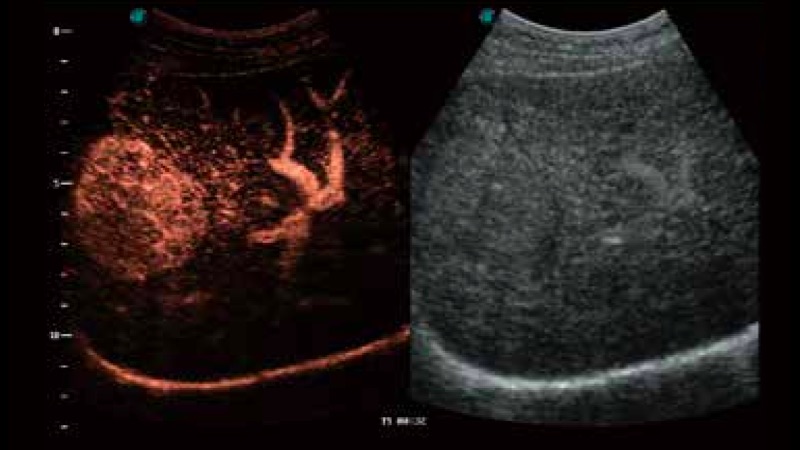

開立醫(yī)療通過不斷的技術(shù)創(chuàng)新,為大眾的生命健康提供持續(xù)關(guān)愛。P12 Plus采用全新一代超聲成像平臺(tái),新平臺(tái)旨在將真實(shí)還原組織解剖結(jié)構(gòu)作為首要目標(biāo)。平臺(tái)采用全新集成化硬件模塊,搭載新一代芯片,系統(tǒng)性能得到大幅提升,為您的診斷提供了豐富的臨床信息。優(yōu)異的圖像表現(xiàn),豐富的探頭配置,全面的應(yīng)用功能,為您日常診斷提供了可靠的助手。

彩色多普勒超聲診斷系統(tǒng)